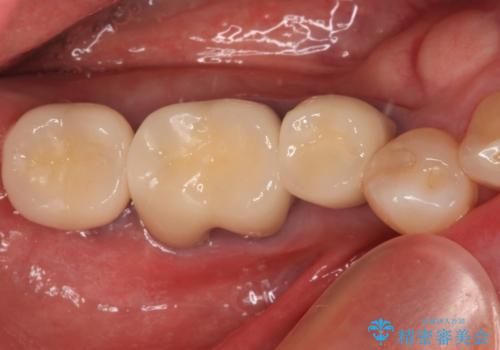

不適な樹脂の詰め物 被せ物で被覆

担当医 岡田康成